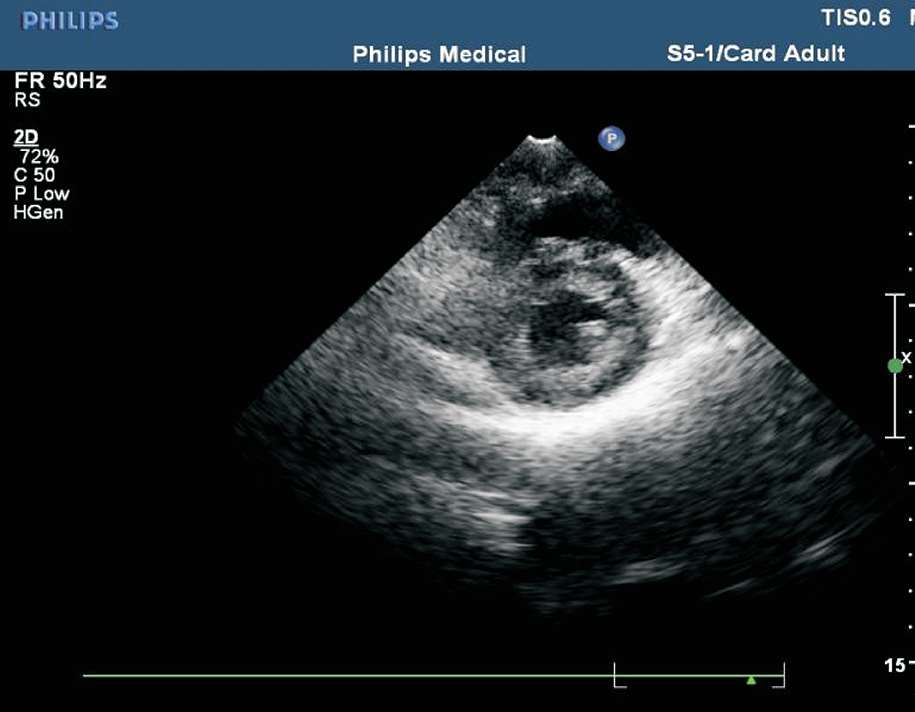

(7)常用的室壁分段方法为16段法。左心室长轴切面将左心室分为3等分:基底段、中间段及心尖段。基底段、中间段短轴切面分为6 等分:左心室前壁、左心室侧壁、左心室后壁、左心室下壁、后间隔及前间隔(见图1-38)。心尖段短轴切面分为4等分:左心室前壁、左心室侧壁、左心室下壁及室间隔(见图1-39)。

图1-39 心尖段短轴切面分4等分